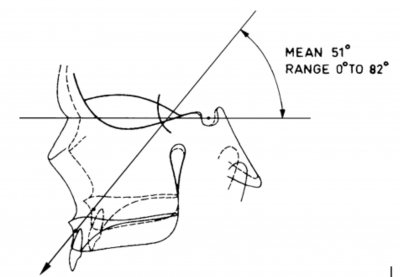

This kinda reminds me of the mew indicator line, indicator cheek line and what'd he go about evaluating SN line, FN plane and Cranial base angles

This kinda reminds me of the mew indicator line, indicator cheek line and what'd he go about evaluating SN line, FN plane and Cranial base angles

View attachment 4063432View attachment 4063433View attachment 4063434View attachment 4063436View attachment 4063438View attachment 4063439View attachment 4063440